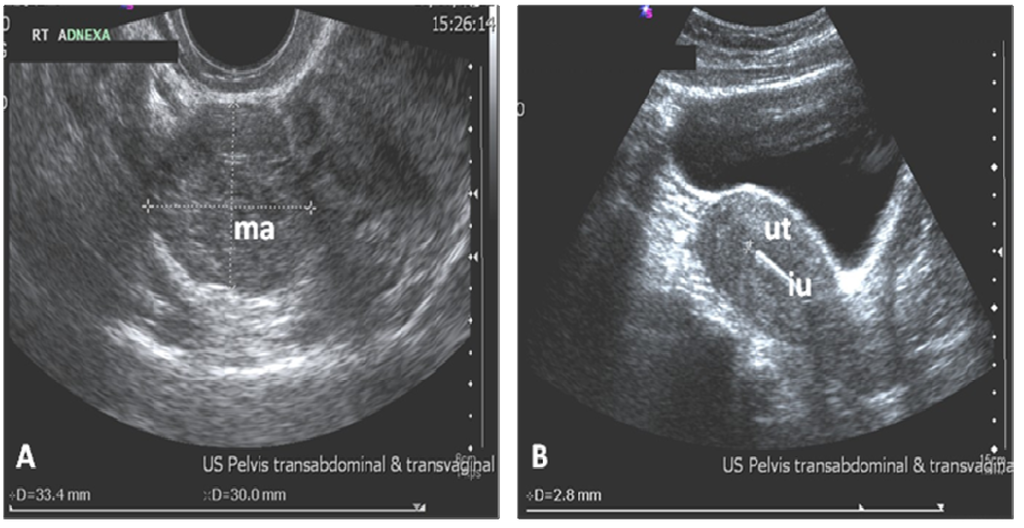

2. Case